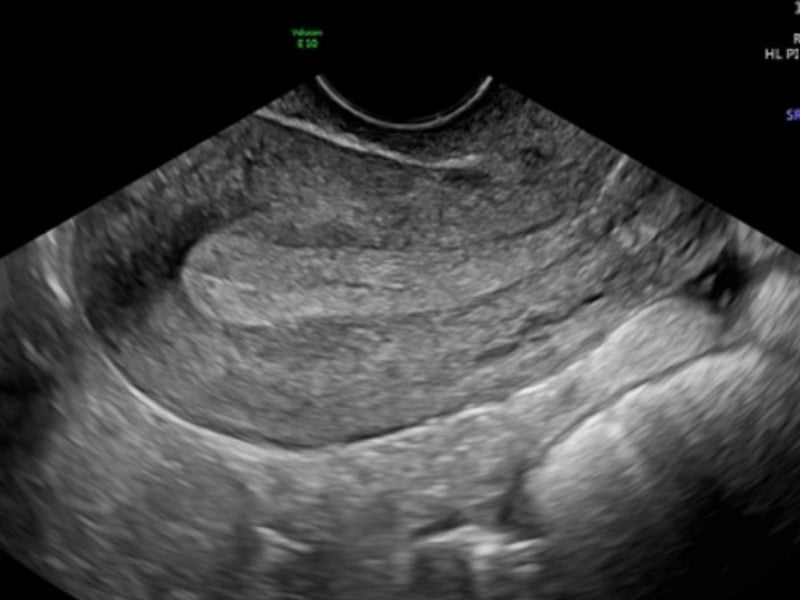

Để đánh giá tình trạng niêm mạc tử cung, các bác sĩ thường sử dụng phương pháp siêu âm đầu dò qua âm đạo để đo chiều dày của lớp niêm mạc. Thông thường, chiều dày này thay đổi theo chu kỳ, phản ánh sự chuẩn bị của nội mạc tử cung để đón nhận trứng thụ tinh. Thang đo về độ dày của niêm mạc rất quan trọng trong việc chẩn đoán các vấn đề liên quan đến khả năng sinh sản.

Theo các tiêu chuẩn y học, độ dày lý tưởng của niêm mạc tử cung trong thời kỳ rụng trứng là khoảng 8-14mm. Khi lớp niêm mạc nằm trong khoảng này, khả năng thụ thai sẽ cao hơn do lớp nội mạc đủ dày để tạo điều kiện thuận lợi cho phôi thai làm tổ. Trước kỳ rụng trứng, độ dày niêm mạc thường tiến triển rõ rệt, qua đó thể hiện khả năng sinh sản của người phụ nữ.

Ngược lại, nếu niêm mạc quá mỏng, thường dưới 7mm, khả năng thụ thai sẽ giảm đi rõ rệt. Tình trạng này có thể do nhiều nguyên nhân như nội tiết không cân đối, tuần hoàn máu kém hoặc tổn thương nội mạc do thủ thuật hoặc viêm nhiễm. Để cải thiện, việc điều chỉnh chế độ dinh dưỡng, phối hợp điều trị y tế sẽ giúp nâng cao độ dày của niêm mạc, hỗ trợ quá trình thụ thai hiệu quả hơn.